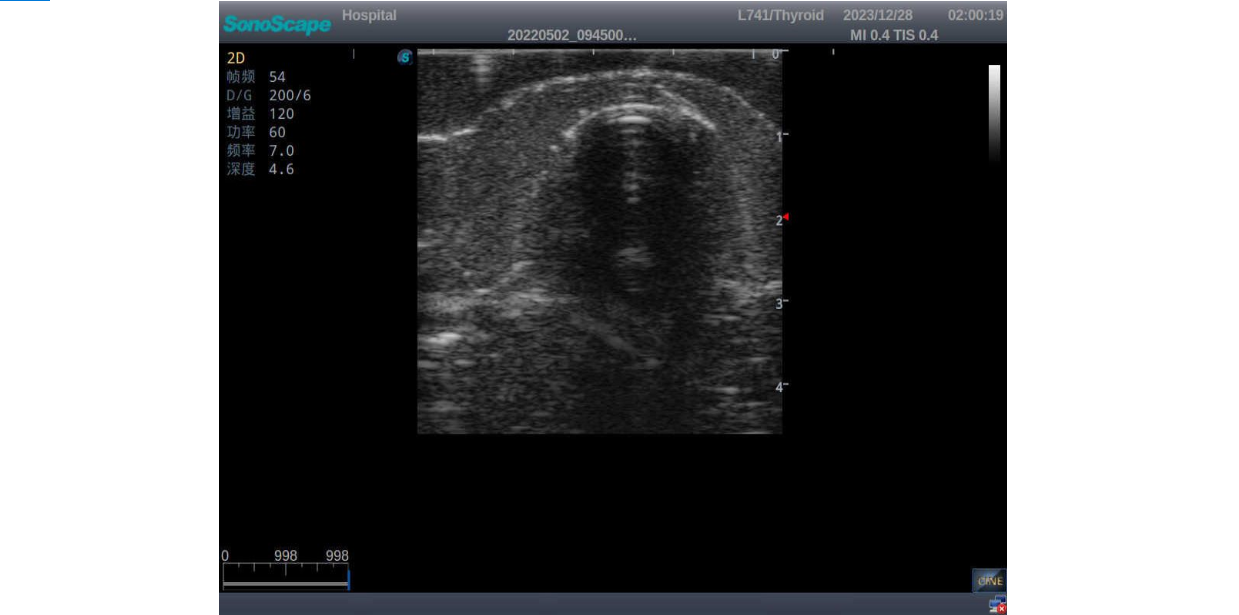

2)       Ultrasonically realistic materials at neck & various types of real ultrasonic machines in clinical available, developing realistic imaging like common carotid artery, internal jugular vein, trachea, thyroid cartilage, cricoid cartilage, lobes of thyroid gland and isthmus

3)       It comes with four (4) thyroid modules and can show five (5) ultrasonic images: normal thyroid, thyroid adenoma, thyroid cancer, nodular goiter, thyroid cyst

Nodular goiter with irregular border and varying sizes of low echo, isoechoic, or high echo nodules